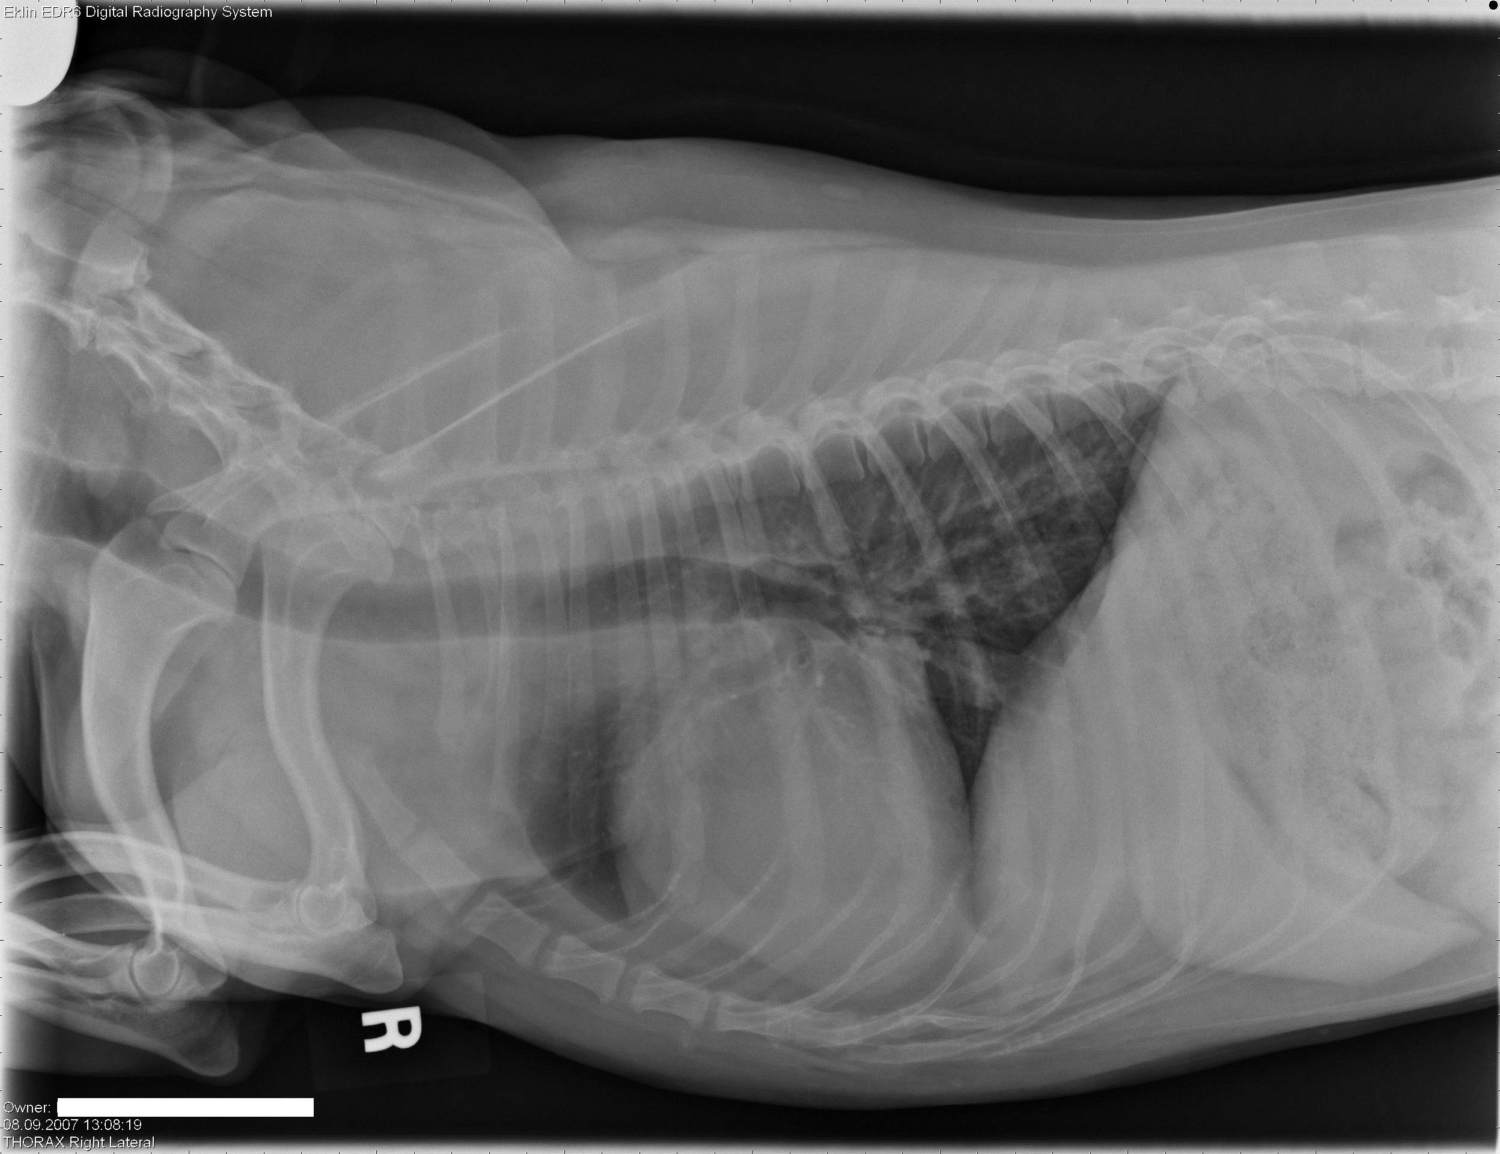

Categorie: Radiologie Quiz

In samenwerking met Dr Adrien-Maxence Hespel van de Universiteit van Tenessee bieden we volgende radiologie quiz aan. Het doel van deze casus is om te…